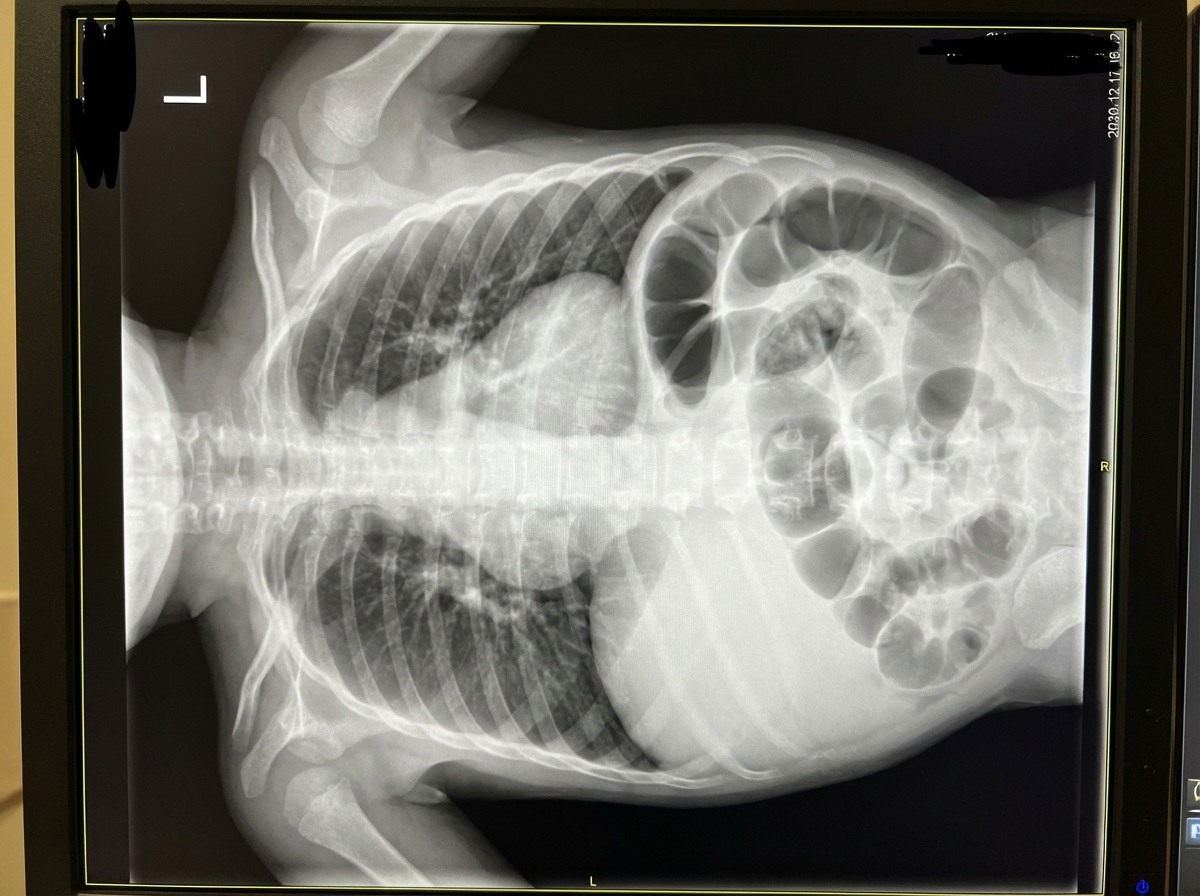

Given the provided X-ray of a neonate, what is the diagnosis?

Explanation: ***Congenital diaphragmatic hernia*** - Classic neonatal chest X-ray shows **bowel loops in the thoracic cavity** with **mediastinal shift** away from the affected side, typically left-sided. - Associated with **pulmonary hypoplasia** and immediate respiratory distress in newborns due to lung compression. *Malrotation* - Primarily an **abdominal condition** affecting bowel positioning around the **superior mesenteric artery**. - Chest X-ray would be normal; diagnosis requires **upper GI series** showing abnormal duodenal positioning. *Pulmonary sequestration* - Shows a **well-defined lung mass** with abnormal **systemic arterial supply** from the aorta. - Does not cause **bowel loops in chest** or immediate severe respiratory distress in neonates. *Pneumatoceles* - Appear as **thin-walled air-filled cysts** within the lung parenchyma, typically following pneumonia. - Do not show **bowel gas patterns** in the chest or cause mediastinal shift.